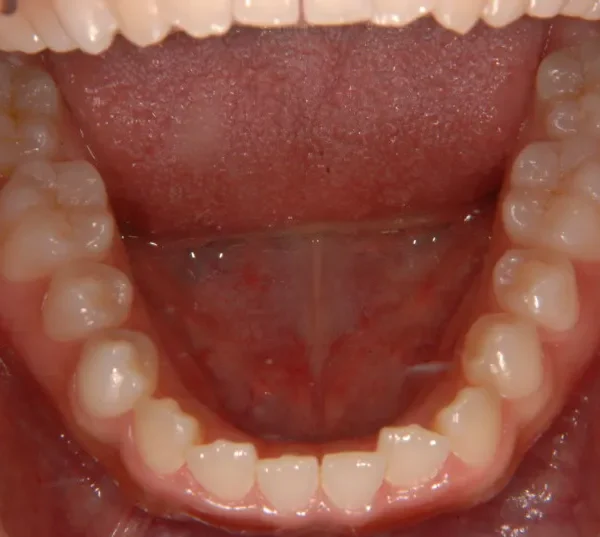

開咬・舌癖・18歳女性

初診時年齢 高校生 (女性) 主訴 開咬 舌癖

状態 前歯で噛めない(開咬/オープンバイト)